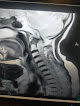

مركز المحطة للأشعة في سوهاج هو وجهتك الموثوقة لتقديم خدمات التصوير الطبي المتقدمة. يتميز المركز بتوفير تقنيات الأشعة الحديثة والمعدات المتطورة، مما يضمن دقة النتائج وسرعة التشخيص. نحن نؤمن بأهمية الرعاية الصحية عالية الجودة، ولذلك نعمل جاهدين لتقديم خدمات متميزة تلبي احتياجات المرضى.

عند اختيارك لمركز المحطة للأشعة، أنت تختار الجودة والاحترافية. نحن نؤمن بأن كل صورة تعكس حالة صحية، ولذلك نسعى لتقديم نتائج دقيقة تساعد الأطباء في اتخاذ القرارات المناسبة لعلاج المرضى. إن خدماتنا تشمل جميع أنواع الفحوصات الشعاعية، مثل الأشعة السينية، والرنين المغناطيسي، والأشعة المقطعية، مما يجعلنا الخيار الأمثل لكل من يبحث عن خدمات أشعة موثوقة في سوهاج.